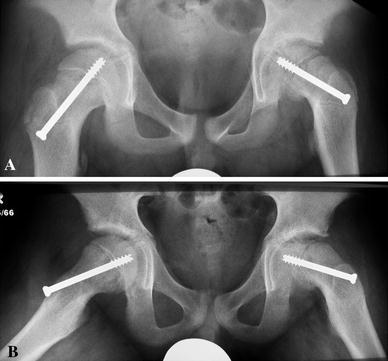

Fig. 1.

a Anteroposterior and b frog-lateral radiographs of a patient with a previous slipped capital femoral epiphysis (SCFE) who was diagnosed with avascular necrosis (AVN) of the femoral head